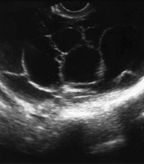

Ultrasound images of multiple septated cysts. Image courtesy of Edward J. Pavlik, director of research in gynecologic oncology, UK Ovarian Screening Research Program.